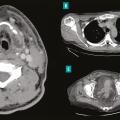

– la présence dans la majorité des cas d’une porte d’entrée à identifier et à traiter dès la phase initiale, avec une importance de l’imagerie pour guider le geste chirurgical (et non pour faire le diagnostic qui reste clinique) [fig. 2 ] ;

– la présence dans la majorité des cas d’une porte d’entrée à identifier et à traiter dès la phase initiale, avec une importance de l’imagerie pour guider le geste chirurgical (et non pour faire le diagnostic qui reste clinique) [

En effet, elles compliquent un foyer infectieux dentaire ou ORL dans respectivement 50 et 20 % des cas, avec une extension médiastinale secondaire objectivée chez 30 % des patients. Cette dernière doit être systématiquement recherchée car elle peut être à l’origine de complications nécessitant dans quelques cas un abord chirurgical thoracique (fig. 2 ).2 Enfin, une thrombose jugulaire n’est pas rare et doit être recherchée sur les examens d’imagerie, en premier lieu un scanner avec injection, afin d’associer un traitement anticoagulant à l’antibiothérapie.

En effet, elles compliquent un foyer infectieux dentaire ou ORL dans respectivement 50 et 20 % des cas, avec une extension médiastinale secondaire objectivée chez 30 % des patients. Cette dernière doit être systématiquement recherchée car elle peut être à l’origine de complications nécessitant dans quelques cas un abord chirurgical thoracique (